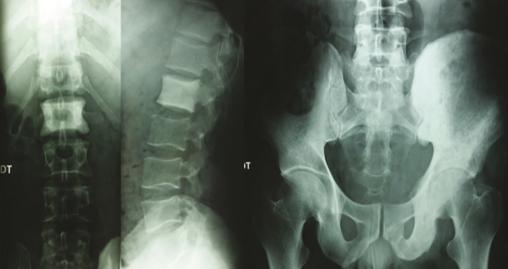

Les radiographies standards mettent en évidence une vertèbre ivoire L1 ainsi qu’une ostéocondensation de l’os iliaque gauche (fig. 1 ). Le scanner thoraco-abdomino-pelvien montre une atteinte osseuse mixte de l’aile iliaque gauche (fig. 2 ), un envahissement des parties molles (avec augmentation des volumes des muscles fessiers et du psoas [fig. 3 ] expliquant la sciatalgie), une néphromégalie unilatérale, une splénomégalie nodulaire et de multiples adénopathies abdomino-pelviennes et thoraciques.

Les radiographies standards mettent en évidence une vertèbre ivoire L1 ainsi qu’une ostéocondensation de l’os iliaque gauche (

Sur les clichés conventionnels, on décrit trois types de lésion : lytique (la plus fréquente avec 50 à 80 % des cas)2, condensante et mixte. L’ostéocondensation isolée est rare (5 % des cas).9 Elle peut réaliser l’aspect classique de la vertèbre ivoire qui est plus fréquemment rencontré dans le lymphome de Hodgkin que dans les lymphomes non hodgkiniens.2 L’association d’une lésion osseuse et d’une importante infiltration des tissus mous en regard alors que la corticale est conservée ou finement mitée est évocatrice du lymphome.9 Dans les cas où l’infiltration lymphomateuse est confinée à la cavité médullaire, les radiographies standards peuvent être normales. La tomographie par émission de positons est l’examen de référence pour evaluer les atteintes osseuses et extra-osseuses.